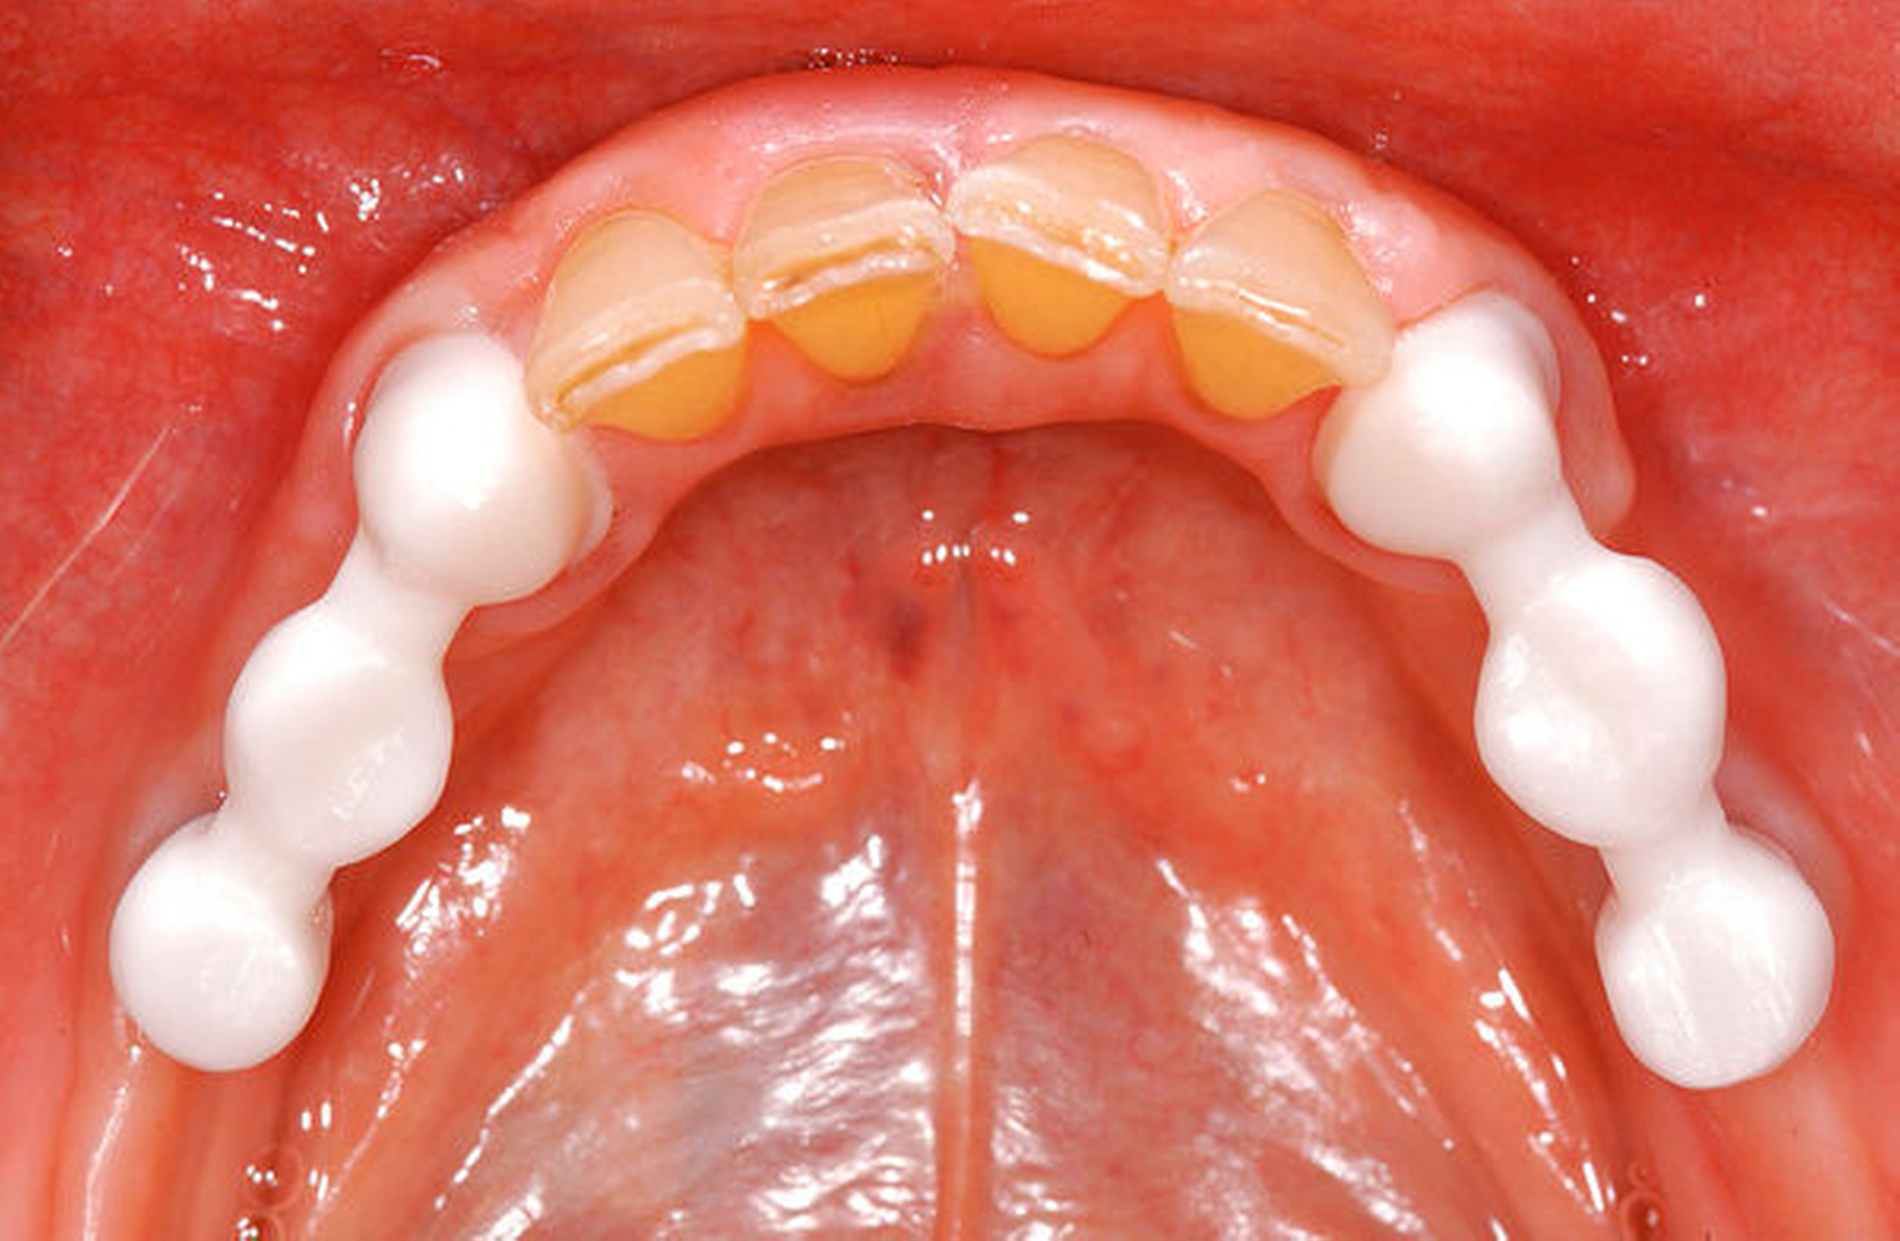

Bei der Rehabilitation von posterior verkürzten Zahnreihen zeigten Verbundbrücken aus verblendeten Zirkonoxidgerüsten nach drei Jahren eine Überlebenswahrscheinlichkeit von 93,9 Prozent (Abbildungen 1 bis 3). Im Rahmen von verschiedenen Studien wurden Überlebensraten für metallbasierte Verbundbrücken nach fünf Jahren zwischen 91,6 und 97,6 Prozent angegeben [Koth et al., 1988; Nickenig et al., 2006; Pieralli et al., 2018], nach zehn Jahren zwischen 81,7 [Mundt et al., 2012] und 87,8 Prozent [Nickenig et al., 2008]. In retrospektiven Untersuchungen, die explizit aus der Analyse der Daten für diese Leitlinie ausgeschlossen wurden, wird von Überlebensraten von bis zu 100 Prozent nach sechs Jahren berichtet [von Stein-Lausnitz et al., 2019].